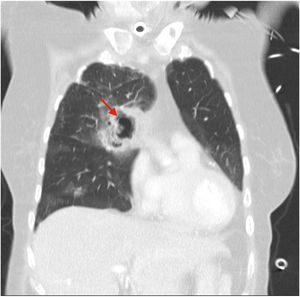

A 70-year-old woman was admitted to our intensive care unit due to COVID-19 pneumonia. She received treatment with remdesivir for five days, two doses of tocilizumab and methylprednisolone (1mg/kg/day). Patient required intubation and tracheostomy due to myopathy. After nineteen days, patient presented a massive hemoptysis. An urgent bronchoscopy evidenced a non-occlusive clot in the right main bronchus and a pulsatile lesion underneath. The pulmonary artery angiography showed a pseudoaneurysm in a right intercostobronchial trunk (Fig. 1) with extravasation of iodinated contrast (red star). Immediate transcatheter exclusion of the pseudoaneurysm was successful. The thoracic CT-scan evidenced the typical COVID-19 pattern with a highly suspicious aspergillus cavity (red arrow) in the right upper lobe pulmonary parenchyma (Figs. 2 and 3). Respiratory secretions cultures were positive for Aspergillus niger so dual antifungal treatment was started. This case illustrates the risk of COVID-19 associated pulmonary aspergillosis (CAPA) and related complications.